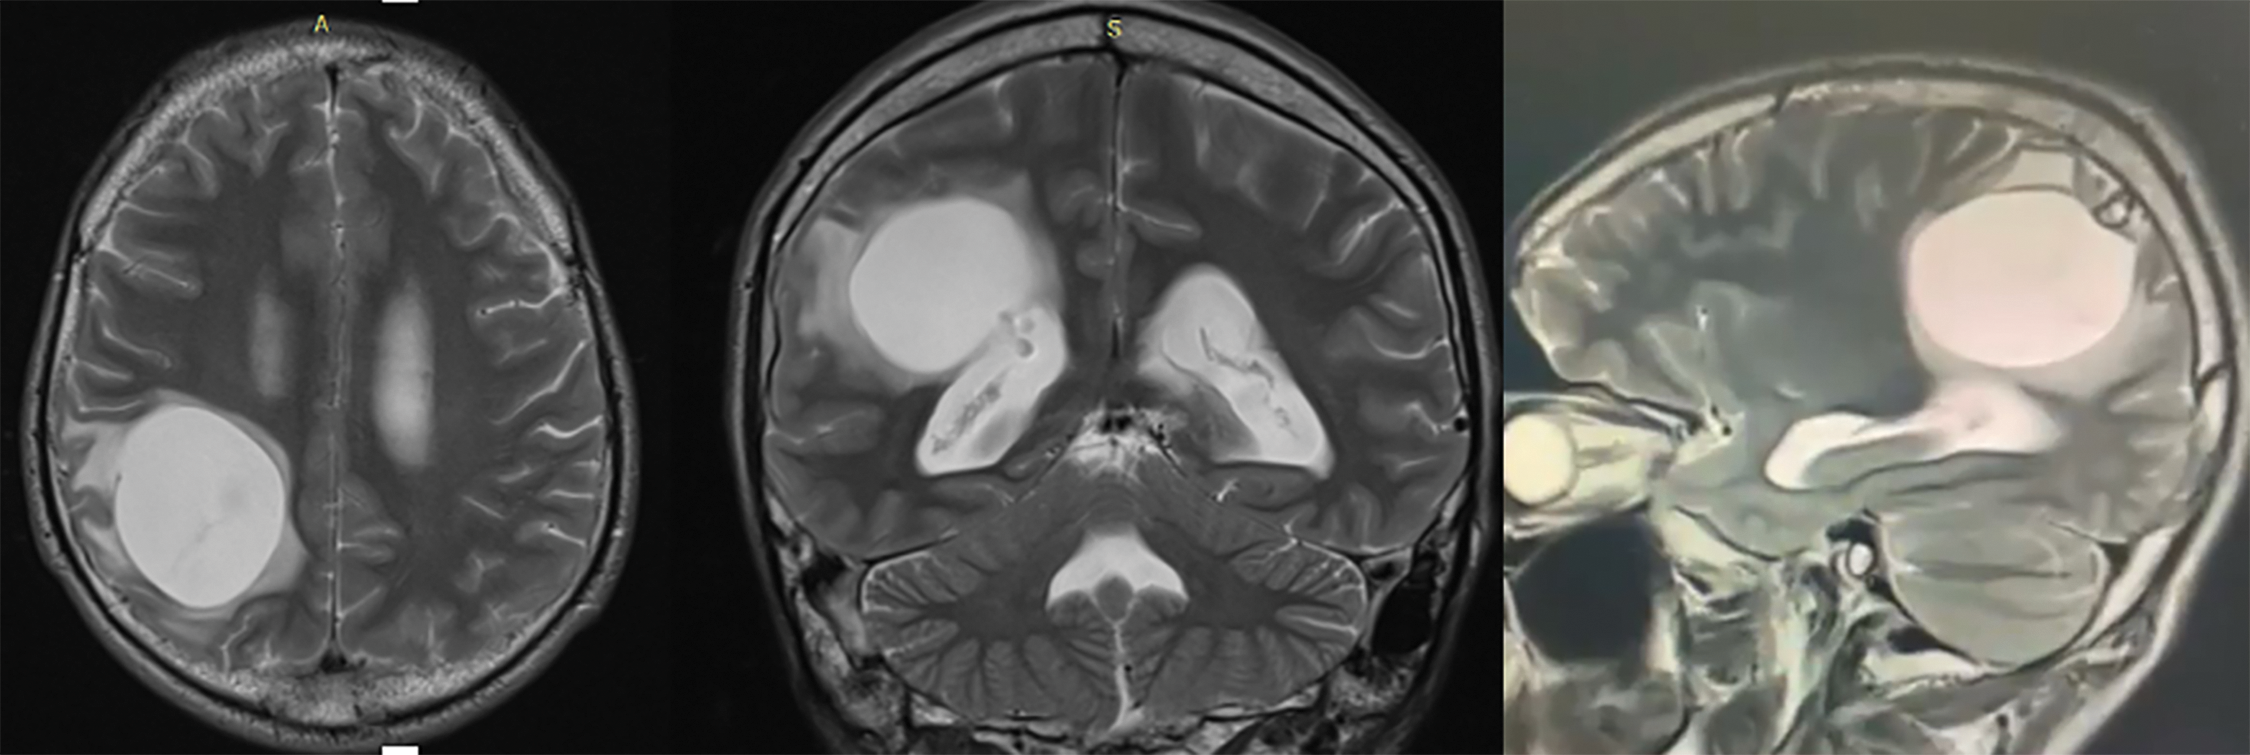

An MRI brain was performed in addition to the CT scan. It confirmed the voluminous cystic mass, intra parenchymatous of right parietal lobe, hypersignal in T2 without peri-lesional edema (Fig. 2); on the sequences T1 after injection of gadolinium it is an hyposignal (Fig. 3). It also objectified the compressive character of the lesion with effacement of the posterior horn of the right lateral ventricle. The blood count revealed a non-specific eosinophilia hyper. Hydatid serology was not performed.

Fig. 3. T1 sequence brain MRI visualizing well-limited cerebral hydatic cyst.

Imaging is essential in the positive diagnosis and pre-therapeutic assessment of cerebral hydatic cyst. X-ray of the skull was not performed in our case; but authors report a voluminous calcification of the cranial vault visualized on radiography corresponding to a calcified cerebral hydatid cyst [12]. The current diagnostic tools are CT and MRI brain. The CT scan cerebral is the key examination, making a positive diagnosis of a hydatid brain cyst in almost all cases. It typically shows, as in our observation, a cystic mass, round or oval with clear contours, thin-walled, of density equivalent to that of the cerebrospinal fluid (CSF) associated with an important mass effect [1], [8], [9]. The cerebral hydatid cyst does not usually increase after injection and is not accompanied by perilesional edema [1], [10], [13]. The almost constant absence of peripheral enhancement by contrast product is explained by the thinness of the pericyst in the brain and by the adhesion of the hydatid membrane to the brain [9]. However, cases of hydatid cerebral cyst with contrast uptake and peripheral edema have been reported in the literature [9].

Brain MRI may be essential in the case of a reengineered cyst and will eliminate differential diagnoses. Problems of differential diagnosis may arise especially in cases of cyst rearrangement; these differential diagnoses are: cystic gliomas, arachnoid cysts, other infectious processes; the cyst wall is thick in these cases with or without contrast [19]. An MRI image of an intense iso cyst relative to the cephalospinal fluid in T1 and T2, with an intense hypo wall in T2, and without associated peri-lesional edema, will be characterized by a healthy cerebral hydatic cyst, this is the case in 75% of cases [4]. On the other hand, when there is a peri-lesion edema, hyperintense in T2, with a contrast taking of the wall, the hydatid cyst is said to be complicated, and then arises the problem of differential diagnosis [4]. Brain MRI would better locate and characterize the cerebral hydatic cyst than CT [20]. Other locations may be associated in about 30% of cases [21], including liver and lung particularly, they should be systematically searched for by performing an abdominal ultrasound and a chest x-ray.